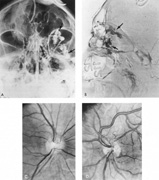

The therapy for AVMs has been reviewed elsewhere.91–93 The preferred treatment remains complete surgical excision of the malformation. However, significant advances in endovascular and radiosurgical techniques have resulted in a marked increase in the use of multimodal, staged approaches to AVM treatment. A variety of intravascular techniques use embolization91 with materials such as particles of polyvinyl alcohol (PVA), platinum coils, and injection of liquid N-butyl-cyanoacrylate (NBCA) adhesive (Fig. 11). Complications of intravascular embolotherapy include vessel perforation by the catheter, migration of embolic materials, and infarction and hemorrhage of normal brain.

Fig. 11. Embolization of middle cerebral vessels that supply occipital lobe arteriovenous malformation (AVM). The patient had a subarachnoid and intraparenchymal hemorrhage that produced a left homonymous field defect. A: Right carotid arteriogram demonstrates contribution via posterior communicating artery to a right occipital lobe AVM. B: Vertebral injection. The arrow points to the enlarged right posterior cerebral artery that is a major feeder of the AVM. C: Right carotid arteriogram during glue embolization procedure. The arrow points to a catheter as it traverses the segment seen in (B). The catheter was advanced via the internal carotid artery but is positioned far posteriorly. D: Upper branches to the AVM now are occluded, with residual low-flow vascularization via the middle cerebral artery. E: Skull film showing radiopaque glue within the AVM and blood vessels previously supplying it. The patient had a persistent visual field defect but greatly reduced headache and no persistence of subjective bruit. (Courtesy of Dr. Joseph Horton.)